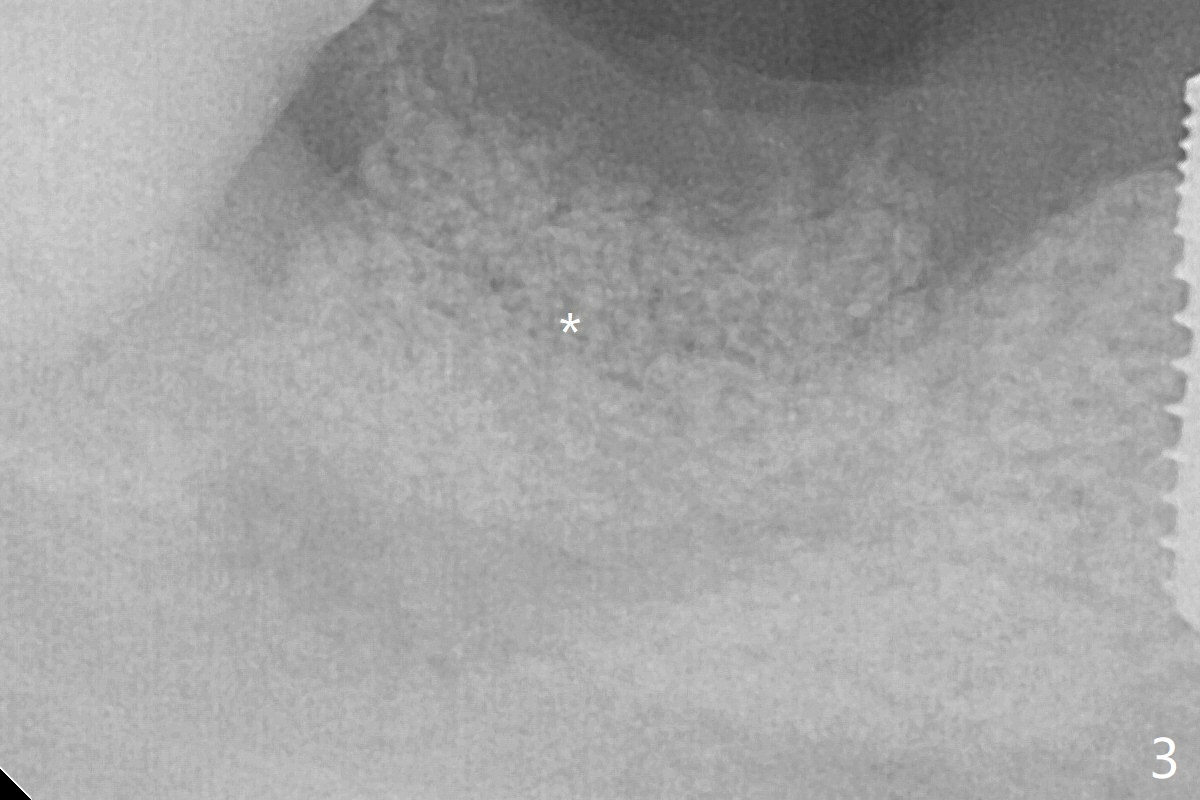

The deep soft tissue socket with hemorrhage after extraction presents difficulty in debridement of granulation tissue apically. After placement of allograft (Fig.3 *) and overlying collagen membrane (Fig.2 C), the socket is closed with 4-0 Chromic gut suture. The bone graft seems to have lost in 8.5 months (Fig.6).